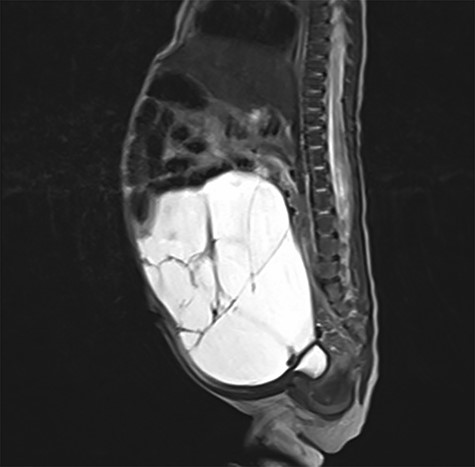

After birth, the male baby presented in good general condition with stable vital signs. The abdomen was distended but not painful on palpation. Postnatal ultrasound confirmed the lesion. To assess the exact extend, MRI was performed showing a macrocystic LM occupying the entire abdomen (Fig. 2) without ascites. However, the exact origin of the lesion and the amount of extension into the mesenteric root could not be described.

Postnatal abdominal MRI. The bowel loops are displaced into the upper part of the abdomen. The exact origin of the lymphatic malformation could not be described.